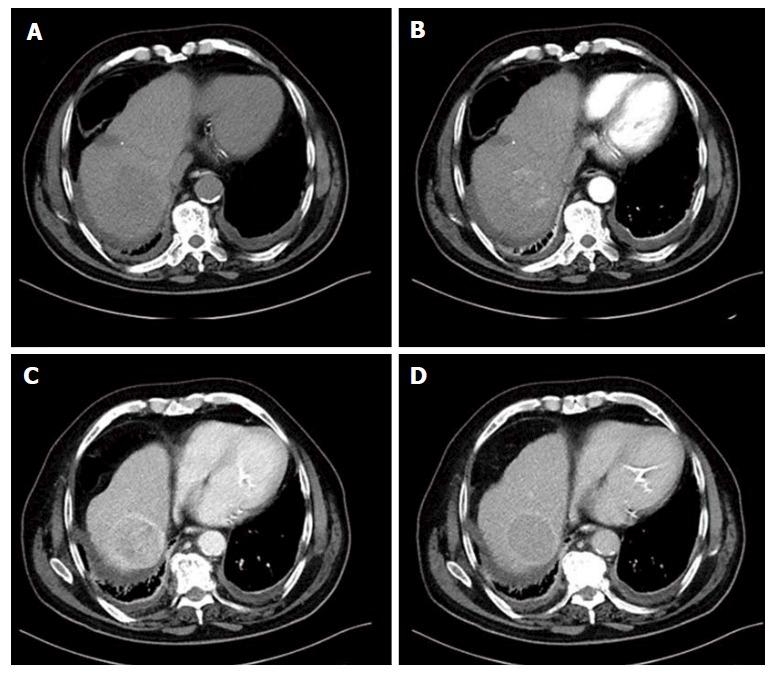

Hepatocellular carcinoma (HCC) is the most frequent primary liver malignancy and the third cause of cancer-related death in the Western Countries. The well-established causes of HCC are chronic liver infections such as hepatitis B virus or chronic hepatitis C virus, nonalcoholic fatty liver disease, consumption of aflatoxins and tobacco smocking. Clinical presentation varies widely; patients can be asymptomatic while symptomatology extends from right upper abdominal quadrant paint and weight loss to obstructive jaundice and lethargy. Imaging is the first key and one of the most important aspects at all stages of diagnosis, therapy and follow-up of patients with HCC. The Barcelona Clinic Liver Cancer Staging System remains the most widely classification system used for HCC management guidelines. Up until now, HCC remains a challenge to early diagnose, and treat effectively; treating management is focused on hepatic resection, orthotopic liver transplantation, ablative therapies, chemoembolization and systemic therapies with cytotocix drugs, and targeted agents. This review article describes the current evidence on epidemiology, symptomatology, diagnosis and treatment of hepatocellular carcinoma.